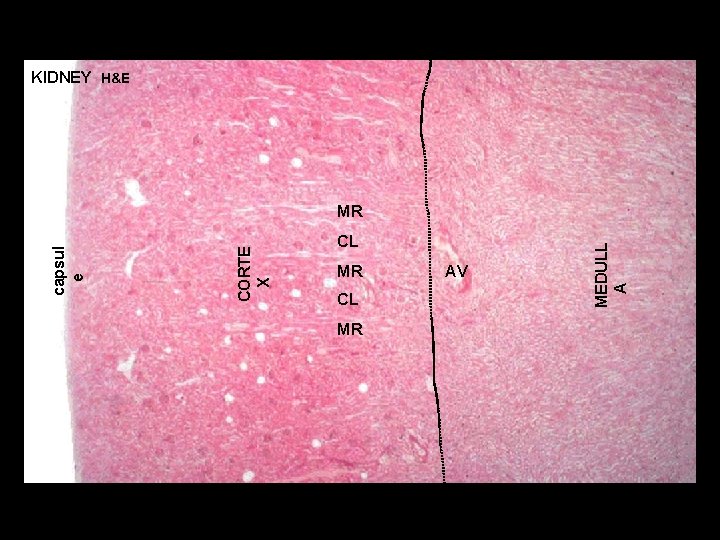

URINARY SYSTEM P KIDNEY (ORGANIZATION) CORTEX P P P - region immediately beneath renal capsule - composed of two distinct regions: P (1) CORTICAL LABYRINTH (2) MEDULLARY RAY P P MEDULL A - located immediately beneath renal cortex - consists of triangular blocks of tissue called the PYRAMIDS - RENAL COLUMNS are strands of cortical tissue that extend down between adjacent pyramids RC

URINARY SYSTEM Cortical Labyrinth with interdigitating Medullary Rays KIDNEY (ORGANIZATION) P RENAL LOBE - a single pyramid with its associated overlying cortex P P P RENAL LOBULE - defined within cortex and involves a single medullary ray (central axis of lobule) with adjacent cortical labyrinth - defined as a functional unit that consists of a collecting duct and all the nephrons that it drains P P P

KIDNEY H&E CL MR AV MEDULL A CORTE X capsul e MR